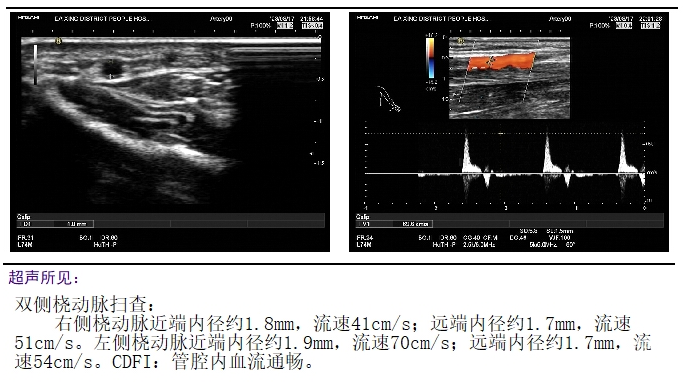

治疗术前完善桡动脉彩超,评估桡动脉路径情况。